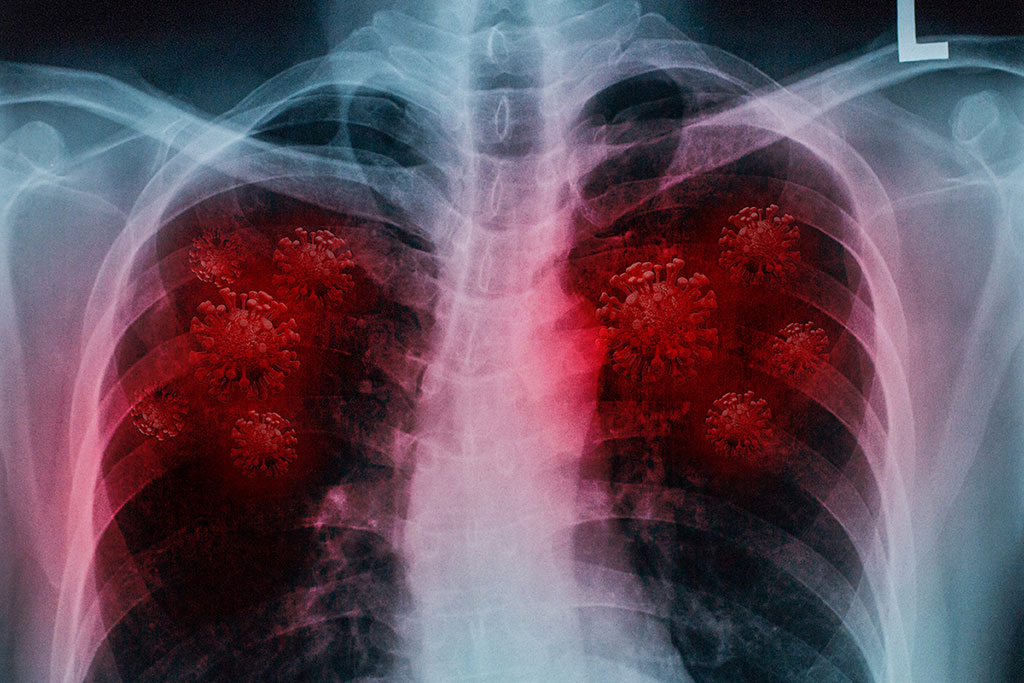

In the study, researchers have demonstrated that the algorithm co-developed by the University of Central Florida (Orlando, FL, USA) could be trained to classify COVID-19 pneumonia in computed tomography (CT) scans with up to 90% accuracy, as well as correctly identify positive cases 84% of the time and negative cases 93% of the time.

Illustration

CT scans offer a deeper insight into COVID-19 diagnosis and progression as compared to the often-used reverse transcription-polymerase chain reaction, or RT-PCR, tests. These tests have high false negative rates, delays in processing and other challenges. Another benefit to CT scans is that they can detect COVID-19 in people without symptoms, in those who have early symptoms, during the height of the disease and after symptoms resolve. However, CT is not always recommended as a diagnostic tool for COVID-19 because the disease often looks similar to influenza-associated pneumonias on the scans. The new UCF co-developed algorithm can overcome this problem by accurately identifying COVID-19 cases, as well as distinguishing them from influenza, thus serving as a great potential aid for physicians.

To perform the study, the researchers trained a computer algorithm to recognize COVID-19 in lung CT scans of 1,280 multinational patients from China, Japan and Italy. Then they tested the algorithm on CT scans of 1,337 patients with lung diseases ranging from COVID-19 to cancer and non-COVID pneumonia. When they compared the computer’s diagnoses with ones confirmed by physicians, they found that the algorithm was extremely proficient in accurately diagnosing COVID-19 pneumonia in the lungs and distinguishing it from other diseases, especially when examining CT scans in the early stages of disease progression.